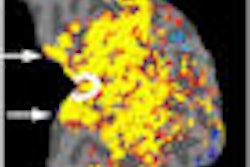

The researchers from the Salt Lake City university developed a protocol to create 3D MR images of the left atrium before radiofrequency ablation, which were processed and analyzed with custom software tools and computer algorithms to calculate the extent of left atrium wall injury.

Six months after the procedure, the researchers found that only 14% had minimal fibrosis and suffered atrial fibrillation recurrence, compared with 75% recurrence for the group that had extensive scar tissue damage.